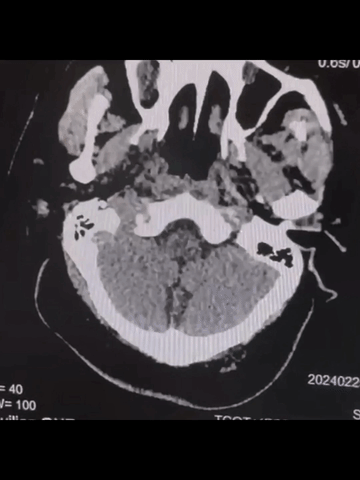

急诊多模式CT

颅脑CT平扫:脑白质改变,余未及其他明确异常。

CTA:基底动脉闭塞,双侧胚胎型后交通,基底动脉尖部可见造影剂充盈;弓上血管迂曲明显,双侧椎动脉V1段均见明显曲折,左侧椎动脉颅内段显影不清,但可见右侧椎动脉颅内段延续至基底动脉闭塞近端。

CTP:脑干和小脑广泛TTP延长,但未见明显CBV和CBF严重降低区域。